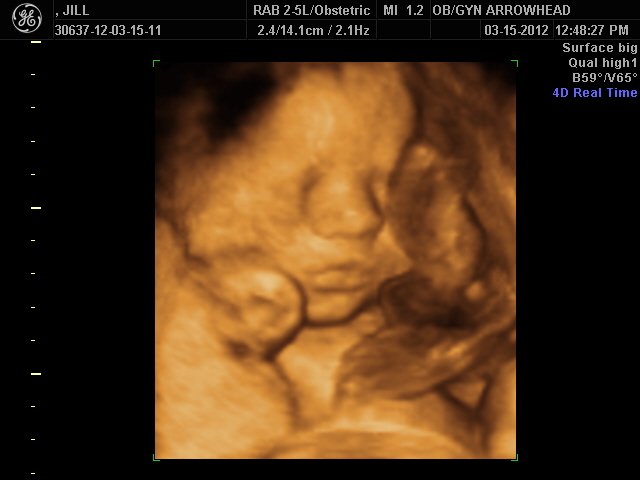

We offer complimentary 3D/4D Ultrasounds to all our OB patients around 30 weeks! The following photos are some examples of our work, shown with permission from our patients.